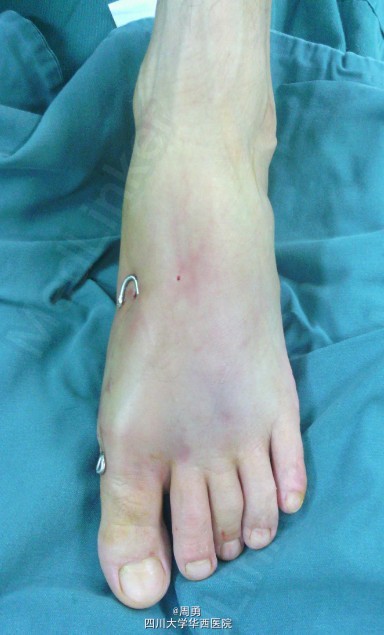

左足第1,2跖骨中近1/3骨折闭合复位克氏针内固定术

此手术为做博士住院总时所做,复位比较满意,价格便宜,效果确实。病例简介:33Y,M,诊断:左足第1,2跖骨中近1/3骨折;处理:行闭合复位克氏针内固定术。